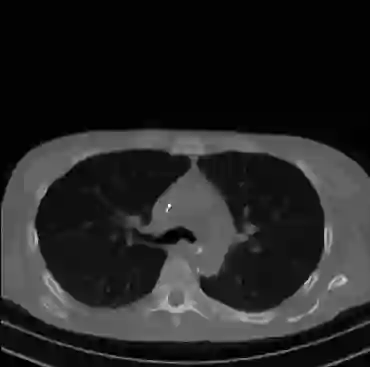

Early and reliable COVID-19 diagnosis based on chest 3-D CT scans can assist medical specialists in vital circumstances. Deep learning methodologies constitute a main approach for chest CT scan analysis and disease prediction. However, large annotated databases are necessary for developing deep learning models that are able to provide COVID-19 diagnosis across various medical environments in different countries. Due to privacy issues, publicly available COVID-19 CT datasets are highly difficult to obtain, which hinders the research and development of AI-enabled diagnosis methods of COVID-19 based on CT scans. In this paper we present the COV19-CT-DB database which is annotated for COVID-19, consisting of about 5,000 3-D CT scans, We have split the database in training, validation and test datasets. The former two datasets can be used for training and validation of machine learning models, while the latter will be used for evaluation of the developed models. We also present a deep learning approach, based on a CNN-RNN network and report its performance on the COVID19-CT-DB database.